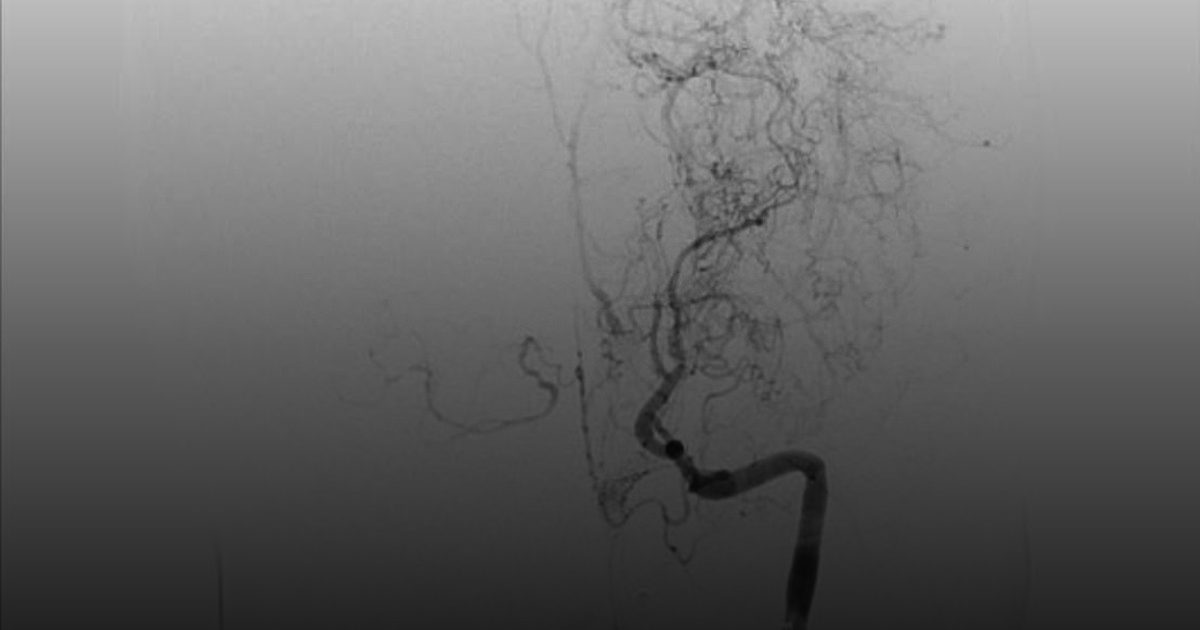

الرياض- واس نجح فريق طبي متخصص في مدينة الملك سعود الطبية – عضو تجمع الرياض الصحي الأول – في إنهاء معاناة طفل يبلغ من العمر خمس سنوات، كان يعاني من جلطات دماغية متكررة، تبيّن لاحقًا أنها نتيجة إصابته بمرض “مويامويا” النادر، وذلك ضمن جهود المدينة في علاج الحالات النادرة والمعقدة. وفي تفاصيل الحالة، أ

بجراحة دقيقة ..“سعود الطبية” تعالج  طفلاً من جلطات دماغية